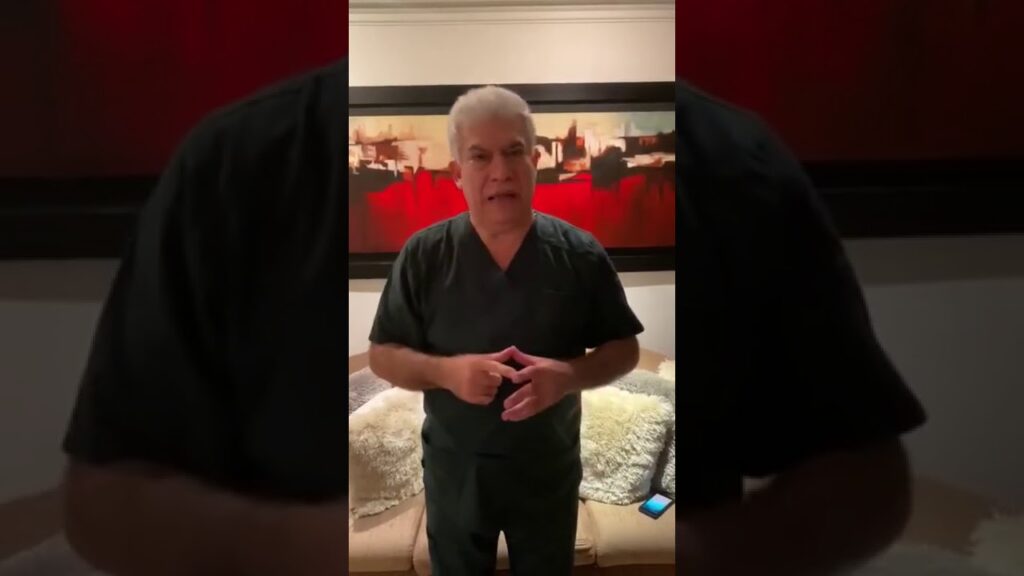

“Era un niño que estaba en asistencia respiratoria mecánica, con 6 meses de edad, y una comorbilidad de patología respiratoria de base. Falleció ayer en la mañana”, le informó a Impacto News el pediatra Gustavo Romero Hany, presidente de la regional Atlántico.

El pediatra aseguró que la idea no es generar pánico, sino lograr que las personas, en especial, los padres de familia, aumenten sus cuidados y protocolos de bioseguridad para proteger a los niños.

“El mensaje es un llamado a la conciencia y responsabilidad a los padres, que si bien es cierto no son tan significativos los casos de menores contagiados en Barranquilla, este es un llamado importante. No es culpa de la Alcaldía, ni de la Gobernación, ni de los hospitales, los padres deben tomar conciencia”, manifestó Romero Hany.